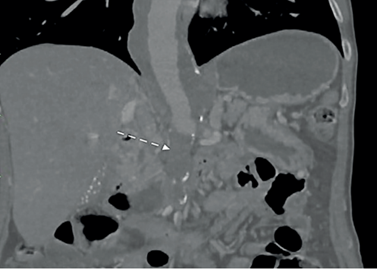

Se abordó inicialmente como posible patología aórtica aguda, con indicación de monitoreo invasivo en unidad de cuidado intensivo (UCI) con soporte con labetalol en infusión continua, con control de cifras tensionales sistólica por debajo de 120 mmHg. Se realizó de carácter emergente tomografía computarizada con protocolo de aorta, en la cual se documentó aneurisma de aorta toracoabdominal Crawford IV de 38x39 mm con oclusión aorto-ilíaca TASC D y oclusión crónica del TC y AMS, con recanalización en el tercio medio de esta última (Figura 1).

Figura 1. Tomografía de abdomen con angiograma donde se observa un aneurisma toracoabdominal y oclusión aorto-ilíaca (flecha).